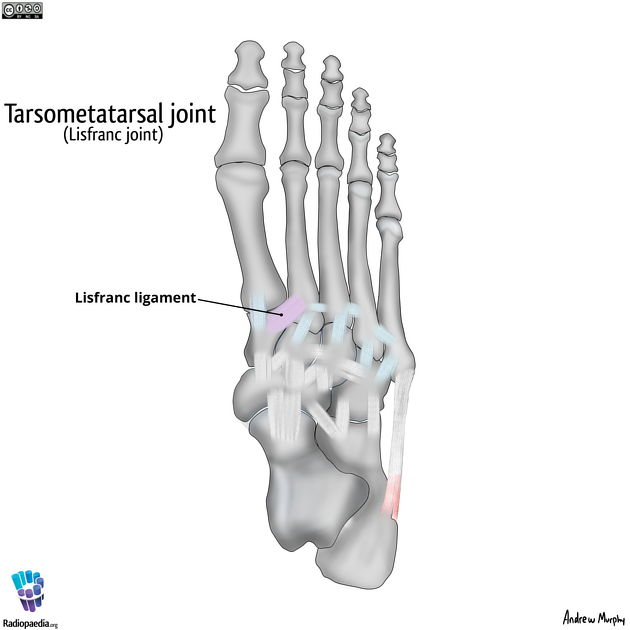

what are the other joints of the foot?

intermetatarsal joints

tarsometatarsal joints

(lisfranc joint)

intertarsal joints

what do the 1,3,4,5th metatarsals do?

they all rotate around the stable 2nd metatarsal

which metatarsal joint is the most stable?

2nd is the most stable joint

what is the lisfranc joint?

medial cuneiform to base of 2nd metatarsal

what are the intertarsal ligaments?

spring ligament

short plantar ligament

long plantar ligament

bifurcate ligament

what is the bifurcate ligament?

supports transverse tarsal metatarsal joint

what are the movements of the bifurcate ligament?

eversion

inversion